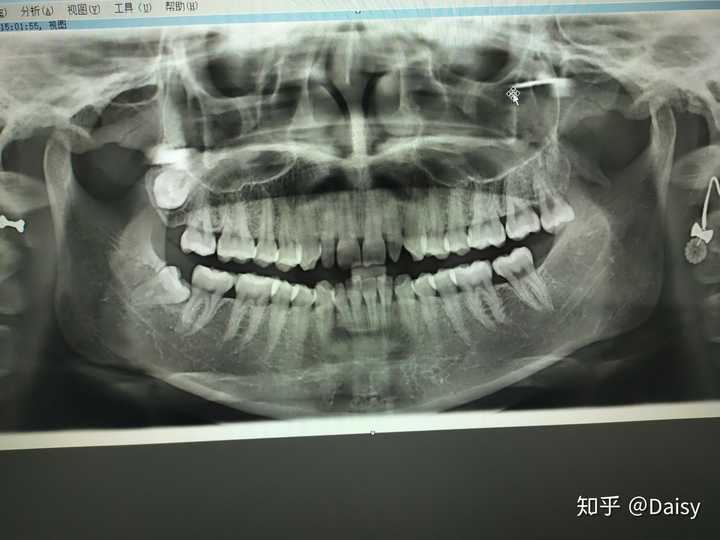

牙片CT,牙片图片

拍牙片出来后,有一个好大的牙长在牙龈里.

牙片常见的有4种:小牙片,全景片,侧位片,口腔ct

由于拔牙,拍了个牙片,显示上牙的右面有个类似囊肿

一般门诊没有,只有专业的口腔医院才有,这种牙片是一种三维ct,比前面

19年12月 洗牙后拍的牙片